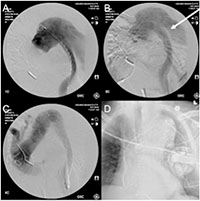

Bilateral femoral artery access was established percutaneously using ultrasound probe and micropuncture technique. A starter wire was advanced under fluoroscopic guidance and placed through the elephant trunk into the ascending aorta using a Simmons 1 catheter. Subsequent intravascular ultrasound interrogation and angiogram using a pigtail confirmed the anatomy (Figure 5A). A “bottom-up” stent grafting strategy was chosen given the significant size mismatch between distal landing zone in mid descending thoracic aorta and the ascending aorta. The first and second stent graft (26 x 22mm and 32 x 28mm, Talent Captivia, Medtronic) were placed in the descending thoracic aorta (Figure 5B). Subsequent exclusion of the transverse aorta was performed using a 36 x 36 x 200mm Valiant Captivia (Medtronic) stent graft (Figure 5C).

An ascending angiogram and intravascular ultrasound imaging confirmed the successful exclusion of the aorta, with lack of blood flow to the false lumen in entire descending thoracic aorta (Figure 5D). The patient remained hemodynamically stable throughout the operation and was transferred extubated to the intensive care unit. His postoperative course was uneventful.

Figure 5: Intraoperative angiogram. A: Preoperative angiogram with the pigtail outside of the elephant trunk. B: Aortogram after deployment of the Talent stent grafts with perfused false lumen. C: Completion angiogram with no endoleak. D: Postoperative X-ray of the chest with the stent graft and the AICD.